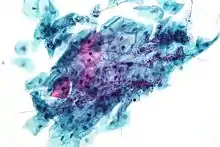

Candida organisms on a pap test. Viral cytopathic effect consistent with herpes simplex virus on a pap test.

Viral cytopathic effect consistent with herpes simplex virus on a pap test. Normal squamous epithelial cells in premenopausal women